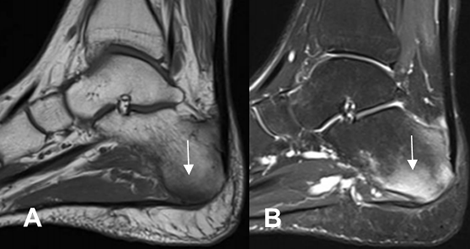

Fig 57 A. Espondilitis anquilosante.

A: RM sagital en T1 y B: RM sagital en STIR. Edema óseo del calcáneo, en un paciente con EA.